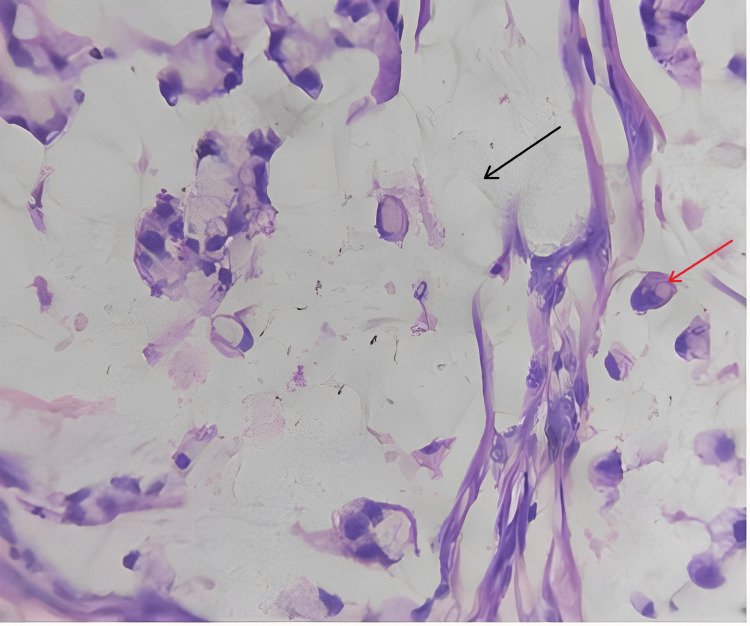

Microscopic findings

Sections studied from the ampullary growth revealed mucosa lined by columnar epithelium infiltrated by diffuse sheets of signet ring cells. These cells had vacuolated cytoplasm and hyperchromatic pleomorphic eccentric nuclei. Areas of mucin pools were seen. A dense inflammatory infiltrate was seen in lamina propria, submucosa, and muscularis propria. The serosa showed inflammatory cells and congested blood vessels. Sections studied from both proximal and distal margins were free from tumor invasion. Sections studied from the duodenum, gall bladder, pancreas, mesentery, and CBD were free from tumor invasion.

Signet ring cell adenocarcinoma of the ampulla of Vater (TisN0M0) Stage 0 (Figures 2–4).